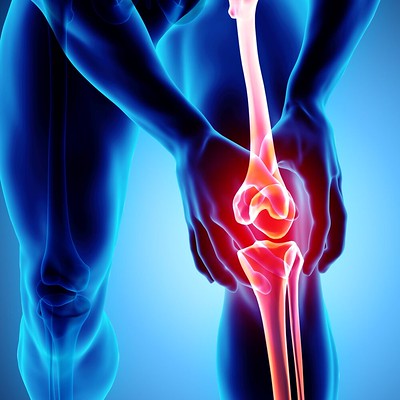

급성 부상은 무릎 통증의 일반적인 원인입니다. 이러한 부상은 스포츠 활동, 낙상 또는 사고 중에 발생할 수 있습니다. 무릎 통증을 유발하는 가장 흔한 급성 손상에는 인대 염좌, 근육 좌상, 반월판 파열 및 골절이 포함됩니다.

과사용 부상은 무릎 통증의 또 다른 일반적인 원인입니다. 이러한 부상은 무릎 관절에 반복적인 스트레스의 결과로 발생합니다. 과사용 부상은 시간이 지남에 따라 점진적으로 발전할 수 있으며 달리기, 뛰기 또는 회전과 관련된 활동을 수행하는 운동선수에게 일반적입니다.

관절염은 관절에 염증을 일으키는 만성 질환입니다. 골관절염, 류마티스 관절염 및 통풍을 포함하여 무릎 관절에 영향을 줄 수 있는 여러 유형의 관절염이 있습니다. 관절염은 무릎 관절에 통증, 부기 및 뻣뻣함을 유발할 수 있습니다.

반월판은 무릎 관절을 완충시키는 연골 조각입니다. 찢어진 반월판은 무릎이 갑자기 비틀리거나 회전하는 결과로 발생할 수 있습니다. 이 부상은 운동선수에게 흔히 발생하며 통증, 부기 및 제한된 이동성을 유발할 수 있습니다.